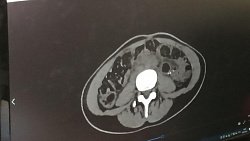

Девушка обратилась к урологам с диагнозом «подковообразная почка». Данная патология встречается примерно у одного из 500 человек. Но в данном случае перешеек посередине почки мешал работе левой половины, которая со временем перестала функционировать и погибла. Длительное время она наполнялась содержимым и достигла объема более двух литров.

«Вся толстая кишка была притеснена этим образованием. Риски ее повреждения были в момент удаления. Люмботомия (через открытый доступ на боку), по моему мнению, крайне плохой вариант, потому что все крупные сосуды закрыты этим образованием. Шансов на аккуратное и безобидное удаление здесь никаких. Лапаротомия (через разрез на животе) лучше, но в данном случае она более травматична. Поскольку пациентка молодая, был выбран единственно возможный вариант», — прокомментировал заведующий отделением урологии ЧОКБ Сергей Кокнаев.